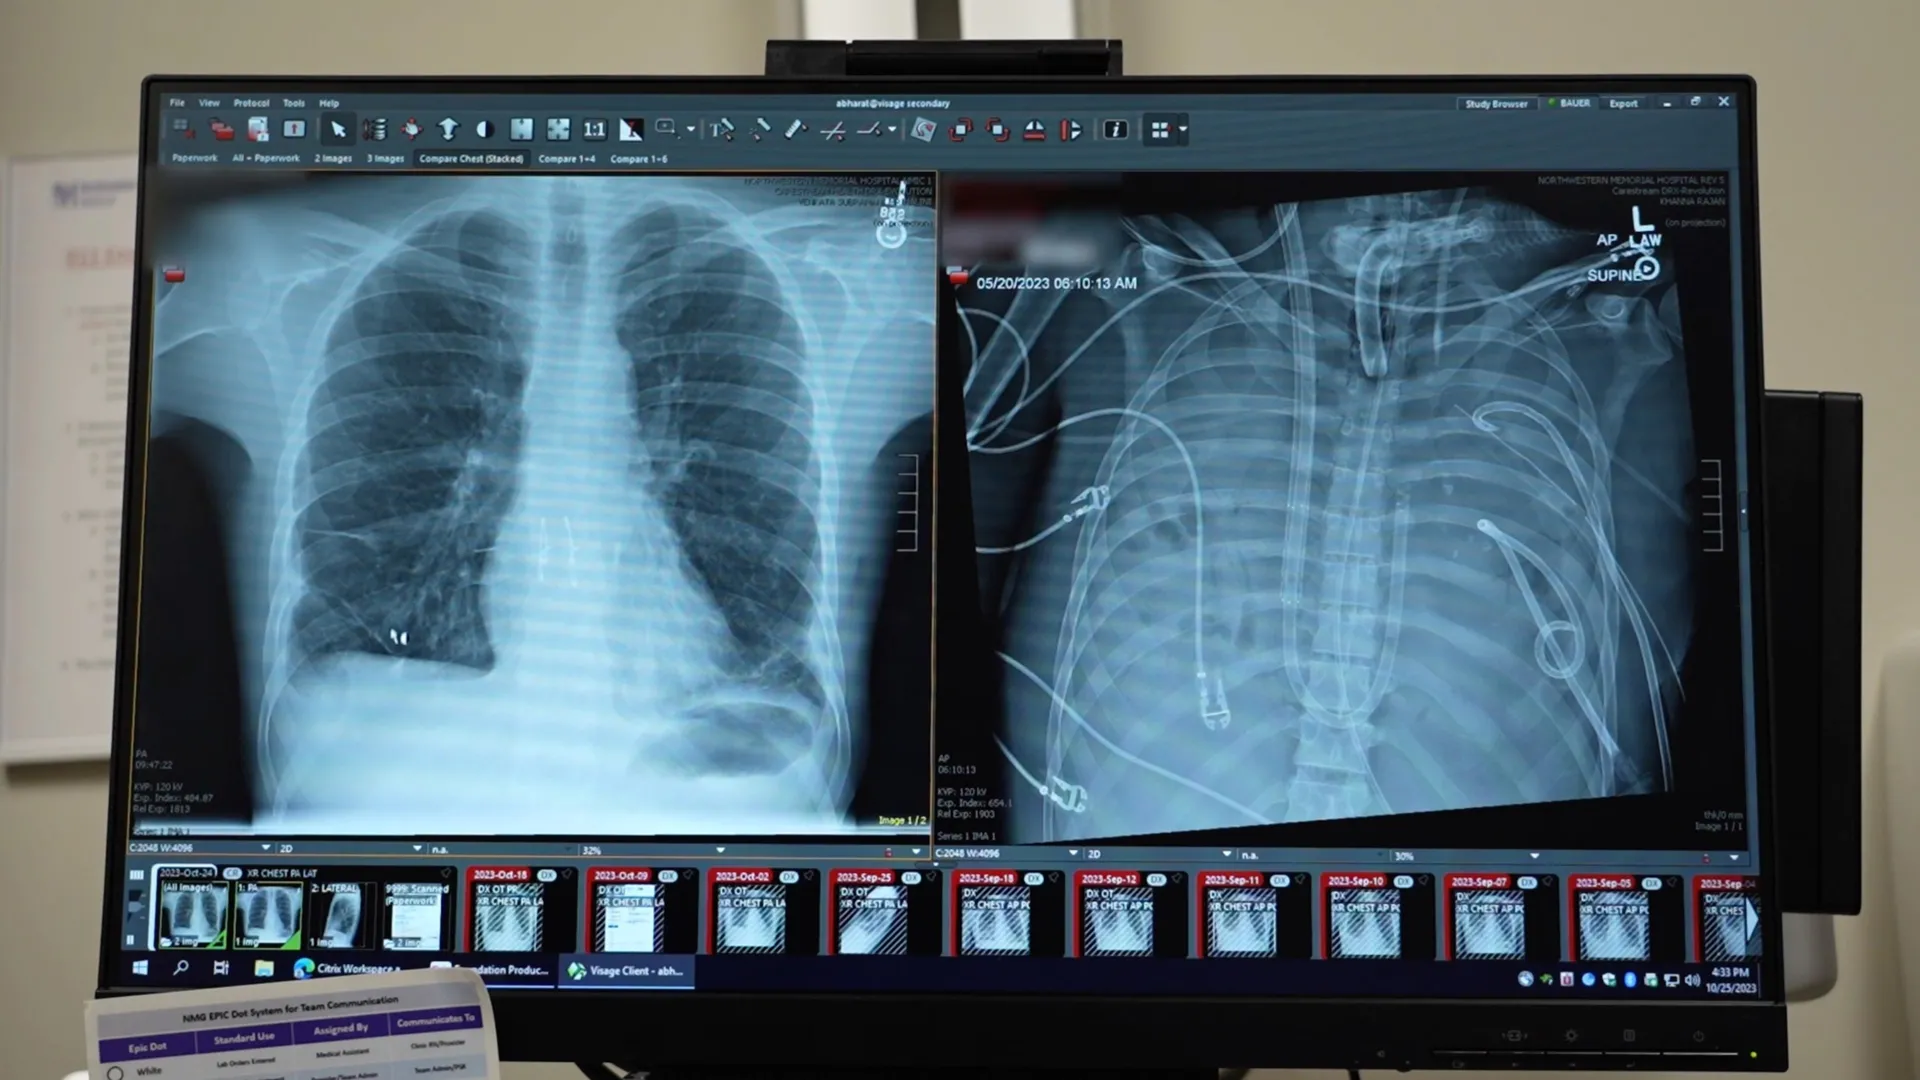

Addressing this unprecedented challenge, the surgical team at Northwestern University, led by thoracic surgeon Ankit Bharat, devised and implemented a sophisticated extracorporeal membrane oxygenation (ECMO) system, specifically configured to function as an "artificial lung." This advanced technology was meticulously engineered to replicate the essential functions of healthy lungs. Blood was drawn from the patient’s body, circulated through the artificial lung where it was infused with oxygen and cleansed of carbon dioxide, and then returned to the bloodstream, effectively bypassing the diseased pulmonary system. This critical intervention provided the necessary physiological support, allowing the patient’s heart and other organs to stabilize and begin a process of recovery, even in the complete absence of native lung function.

Following the surgical removal of his severely infected lungs, the patient’s condition began to show marked improvement. His circulatory system stabilized, his blood pressure normalized, and the overwhelming infection started to recede, bringing the rampant spread of pathogens under control. This period of stabilization, made possible by the artificial lung system, was instrumental in preparing him for the definitive treatment. After a tense 48-hour waiting period, compatible donor lungs became available, and a complex, multi-hour double lung transplant surgery was successfully performed. Remarkably, more than two years post-transplant, the patient has recovered fully and is now living a normal, active life with robust lung function, a profound testament to the efficacy of this integrated approach.